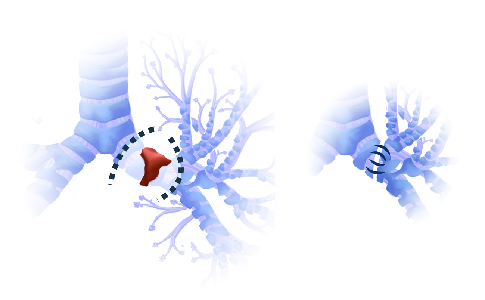

Detailreiche Fotografien aus der medizinischen Praxis ergänzen die Texte; moderne, genaue,

wissenschaftliche Zeichnungen geben Einblick in die Anatomie und die Funktion der Lunge und

anderer Organe.